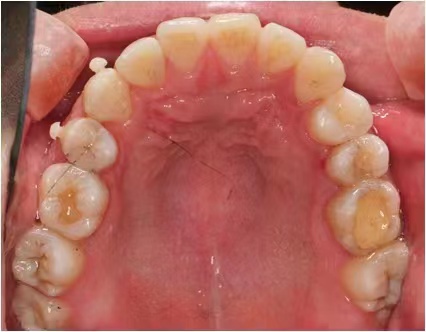

情况:不接受外科手术,在当地做了1年半的矫治,遇到困难无法进行。由外地正畸同行推荐来上海寻求非手术矫治的二手病例。武广增老师接收时的错合畸形情况,呈现严重的骨性反合偏合及侧方开合(图1-图10)。由于推荐其去口腔医院接受正颌外科手术遭到拒绝,武广增老师通过专业的检查、分析,制定一套详细的治疗计划,采用了磨牙推进器技术、武式辅弓技术等特色正畸手段获得明显效果(图2-1~图2-9)。治疗结束后也拍摄了相关照片(图3-1~图3-9)。

矫治前

图1

图2

图3

图4

图5